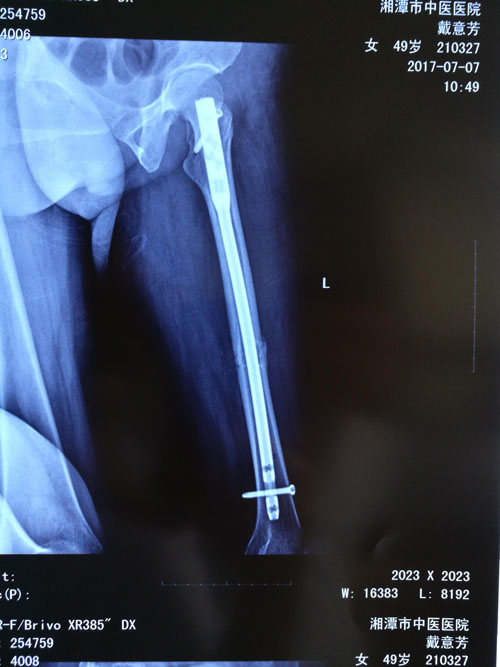

典型病例:閉合復位髓內釘治療股骨骨折,創(chuàng)傷小、出血少,骨折愈合快。